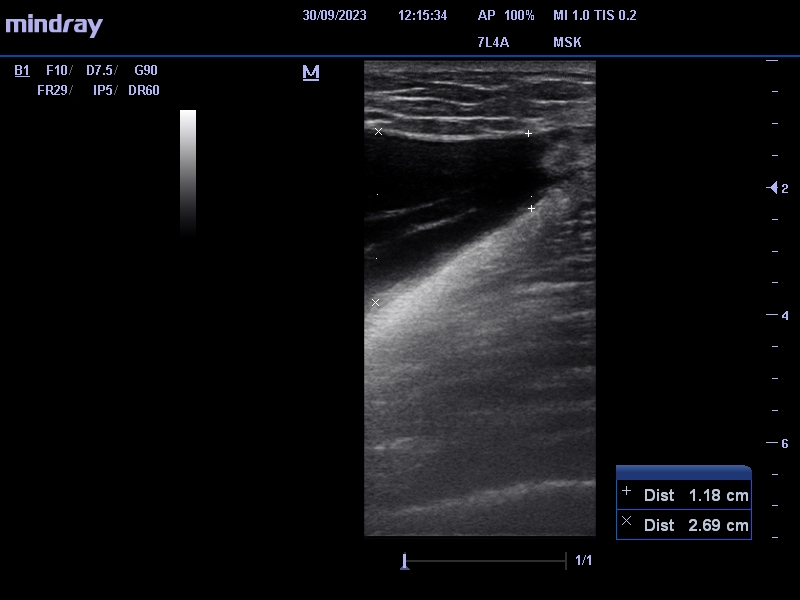

Se identifica entre el tejido celular subcutáneo y la fascia muscular, colección anecogénica, avascular de 2,8 x 17 cm (antero-posterior x craneocaudal) que nos sugiere lesión de Morel-Lavallée.

Ante la sospecha de LML se le deriva a urgencias hospitalarias para drenaje eco-guiado, le realizan punción-aspiración obteniéndose 345 ml de contenido serohemático. Posteriormente le  ponen vendaje compresivo.

Se le cita a los 7 días para control ecográfico, donde le extraen 80 cc de contenido y se le pone de nuevo vendaje compresivo. Nueva revisión a la semana encontrándose asintomático y sin recidiva.